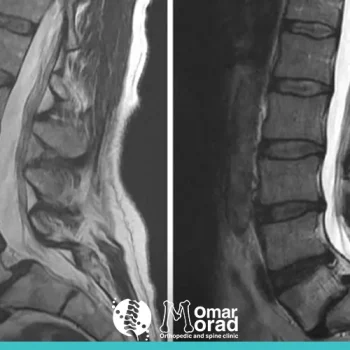

أعراض الانزلاق الغضروفي القطني

أعراض الانزلاق الغضروفي القطني هي أكثر من مجرد ألم عابر في أسفل الظهر؛ إنها مجموعة من الإشارات المزعجة التي يرسلها - اقرأ المزيد..